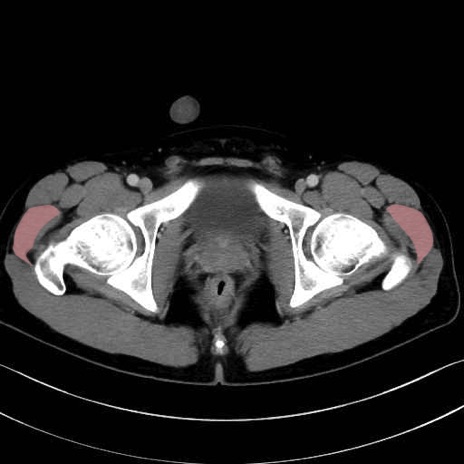

中殿筋(gluteus medius)のCT画像の解剖

中殿筋 (Gluteus medius)